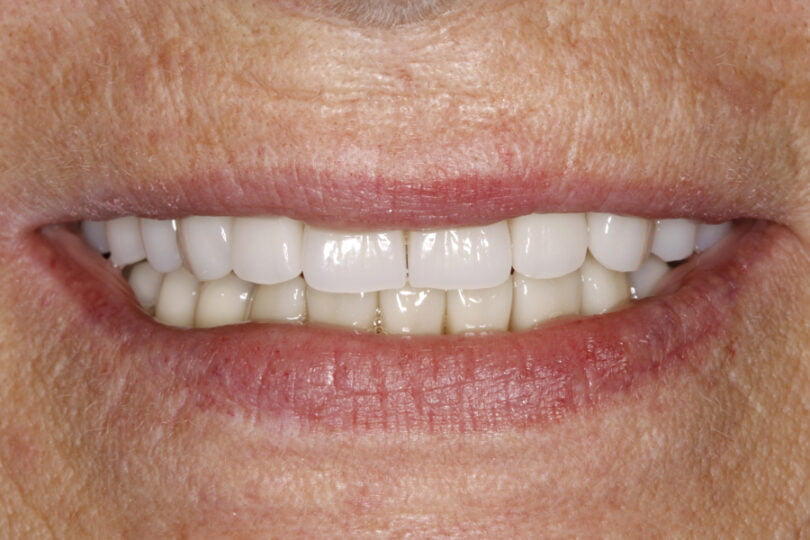

Os resultados obtidos no nosso estudo sobre o CHS indicam-nos que o rácio coroa-implante superior a 3 e o CHS superior a 15 mm não tem nenhum efeito prejudicial para a perda óssea crestal, nem para a sobrevivência dos implantes estudados ou as próteses. No entanto, este parâmetro deve ser tido em consideração para o desenho das reabilitações de modo a evitar tensões crestais excessivas ou desnecessárias.

As seguintes imagens apresentam um dos casos incluídos no estudo (figura 03 – 15).